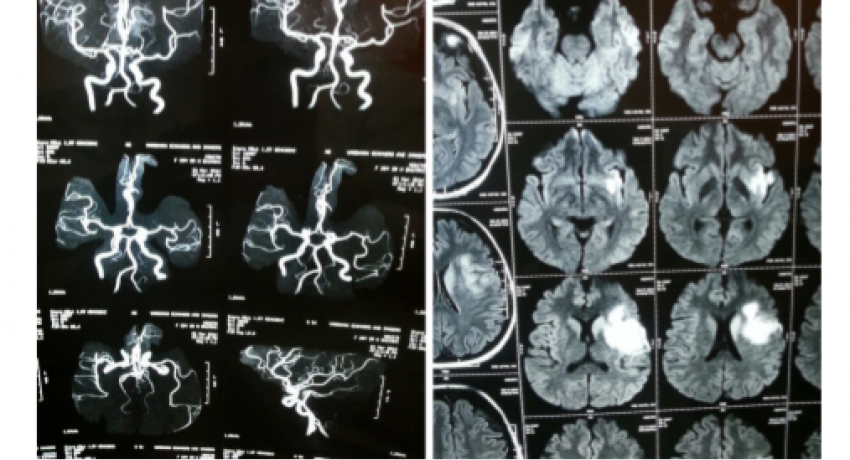

Brain scan showing Infarct